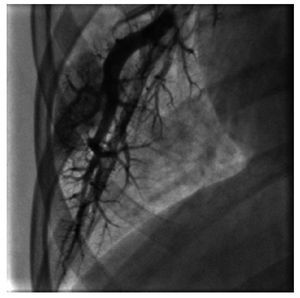

Figura 5 Angiografía pulmonar magnificada en cuña de la rama izquierda. Se observa la mancha capilar heterogénea con amputación de algunos vasos arteriales, en un paciente con anomalía de Ebstein e hipertensión arterial pulmonar.